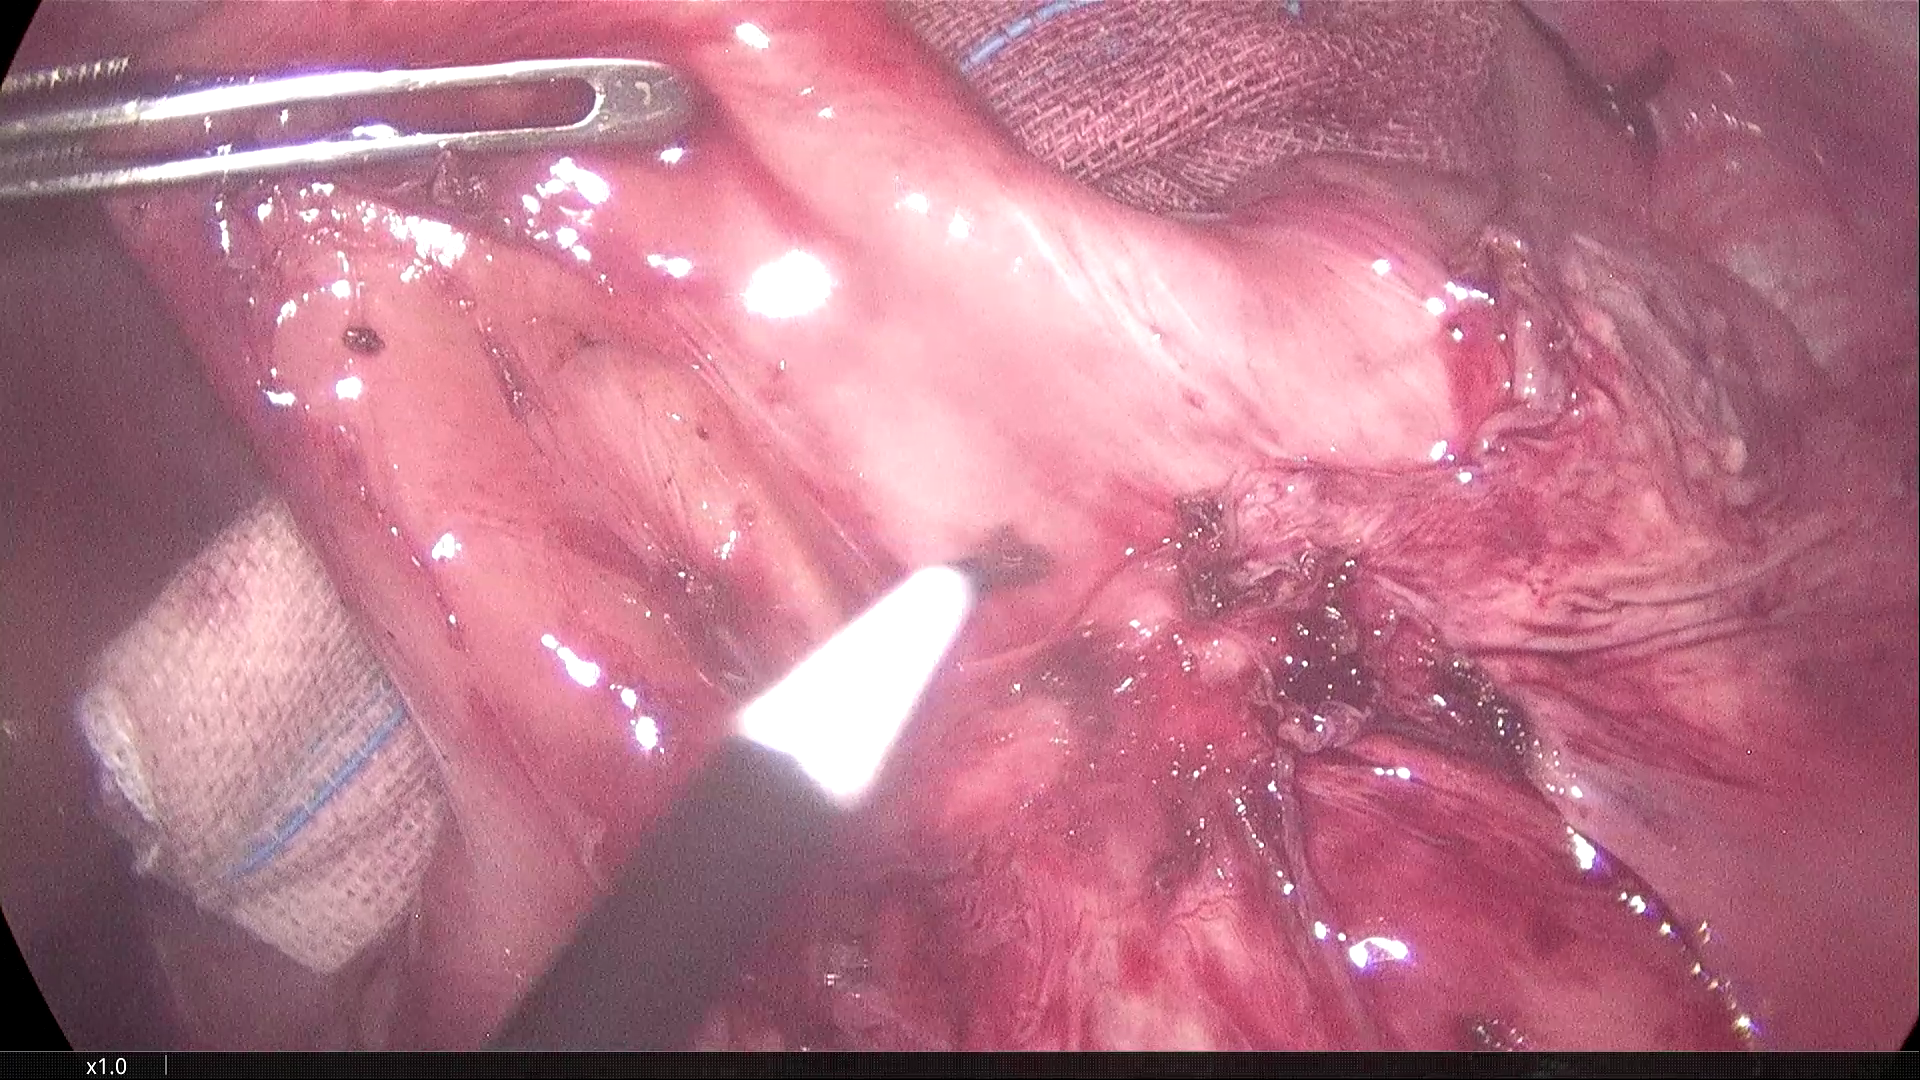

2021-3-31腹腔镜探查,脐部闭合穿刺置入腹腔镜,为观察孔。左下腹及下腹正中分别作操作孔,腹腔镜探查,腹膜光滑,腹腔无积液,胃肠道柔软,空回肠结肠无扩张。无游离大网膜,右下腹无游离肠襻,区域性的回肠肠襻为软膜样组织覆盖包裹,无明显炎症反应。包裹团块张力不高,内侧与乙状结肠系膜呈纤维组织粘连。锐性分离,无明显渗出。自后腹壁锐性切开包膜,显露其内迂曲回肠襻,形态大致正常,与包膜呈一般纤维组织性间隙,易于分离。包膜内肠管间有数条致密粘连纤维索带,予以切除。切除大部包膜组织,完全解放其中的回肠及阑尾远端部分。局部创面少许渗出,自回盲部顺序近端探查检视所有系膜小肠,见肠管及系膜自然正常形态,肠道畅通,未见憩室、肿物及外压扭转等病变。包膜包裹段回肠120cm,肠壁、系膜柔顺无损伤。直肠及盆腔未见明显异常,置腹腔引流管一根。

松解后的效果图